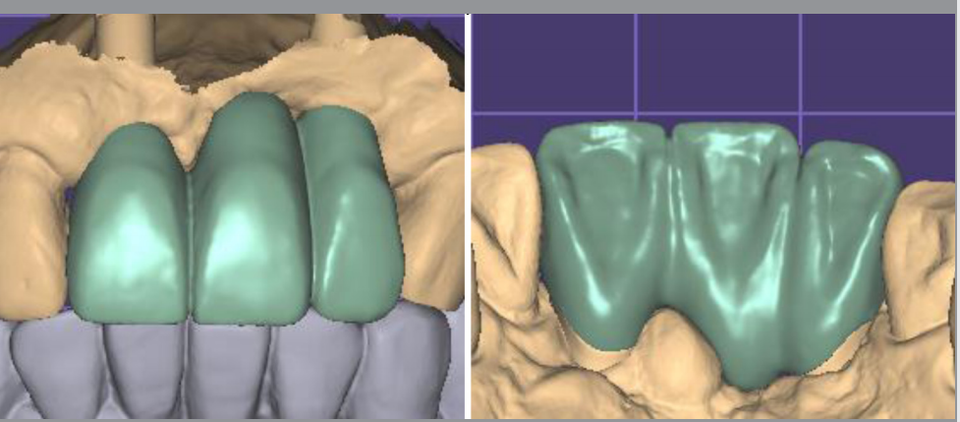

보철 방식도 abutment (스크류 메탈 링크)를 스캔 바디로 사용하기에 디지털 소모품인 스캔바디비용이 들지 않는다.

보철 지대치로 스캔하기 때문에 항상 새 스캔 바디로 스캔하는 격이다.

구강스캐너로 스캔 시 정렬(매칭) 결과는 매우 만족스러웠다. 모델 제작없이 디지털로 상부 제작이 쉬운 이유이다.

세팅값을 조절하기 위해서는 구강 외에서 abutment를 스캔해서 자연치처럼 인식해서 제작해야 modelless로 작업이 가능하다.